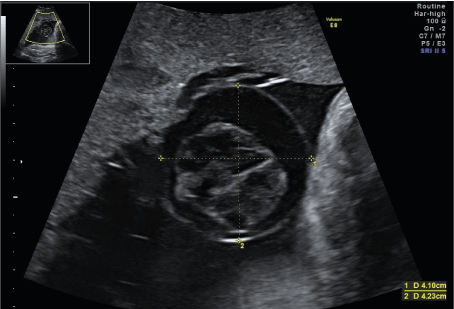

A 33-year-old woman in 32 weeks and 3 days of her third pregnancy was transferred to our unit for immediate delivery due to mayor concerns of her outpatient obstetrician regarding a rapidly developing cystic mass at the base of the placental umbilical cord with significant morphological changes within the last 14 days. The pregnancy had been uneventful up to this point. Sonography showed a timely developed fetus with a normal amount of amniotic fluid and normal Doppler parameters. There was a cystic structure of 42mm x 29mm x 41mm close to the placental insertion of the umbilical cord. Within the anechoic cystic mass, a spherical echo-rich structure of 23mm x 26mm x 28mm on a thin stalk without detectable vascularization was visible (Figures 1 and 2). The cyst was first noticed in the 3rd ultrasound scan at 30 weeks of gestation, but at that time it was still without internal structure. Due to the change in morphology the considered differential diagnosis were a thrombosed extra-abdominal umbilical vein varix as well as a placental or umbilical cord cyst.

Figure 1. Cystic structure of 42mm x 29mm x 41mm close to the placental insertion of the umbilical cord. Within the anechoic cystic mass, a spherical echo-rich structure of 23mm x 26mm x 28mm on a thin stalk without detectable vascularization was visible